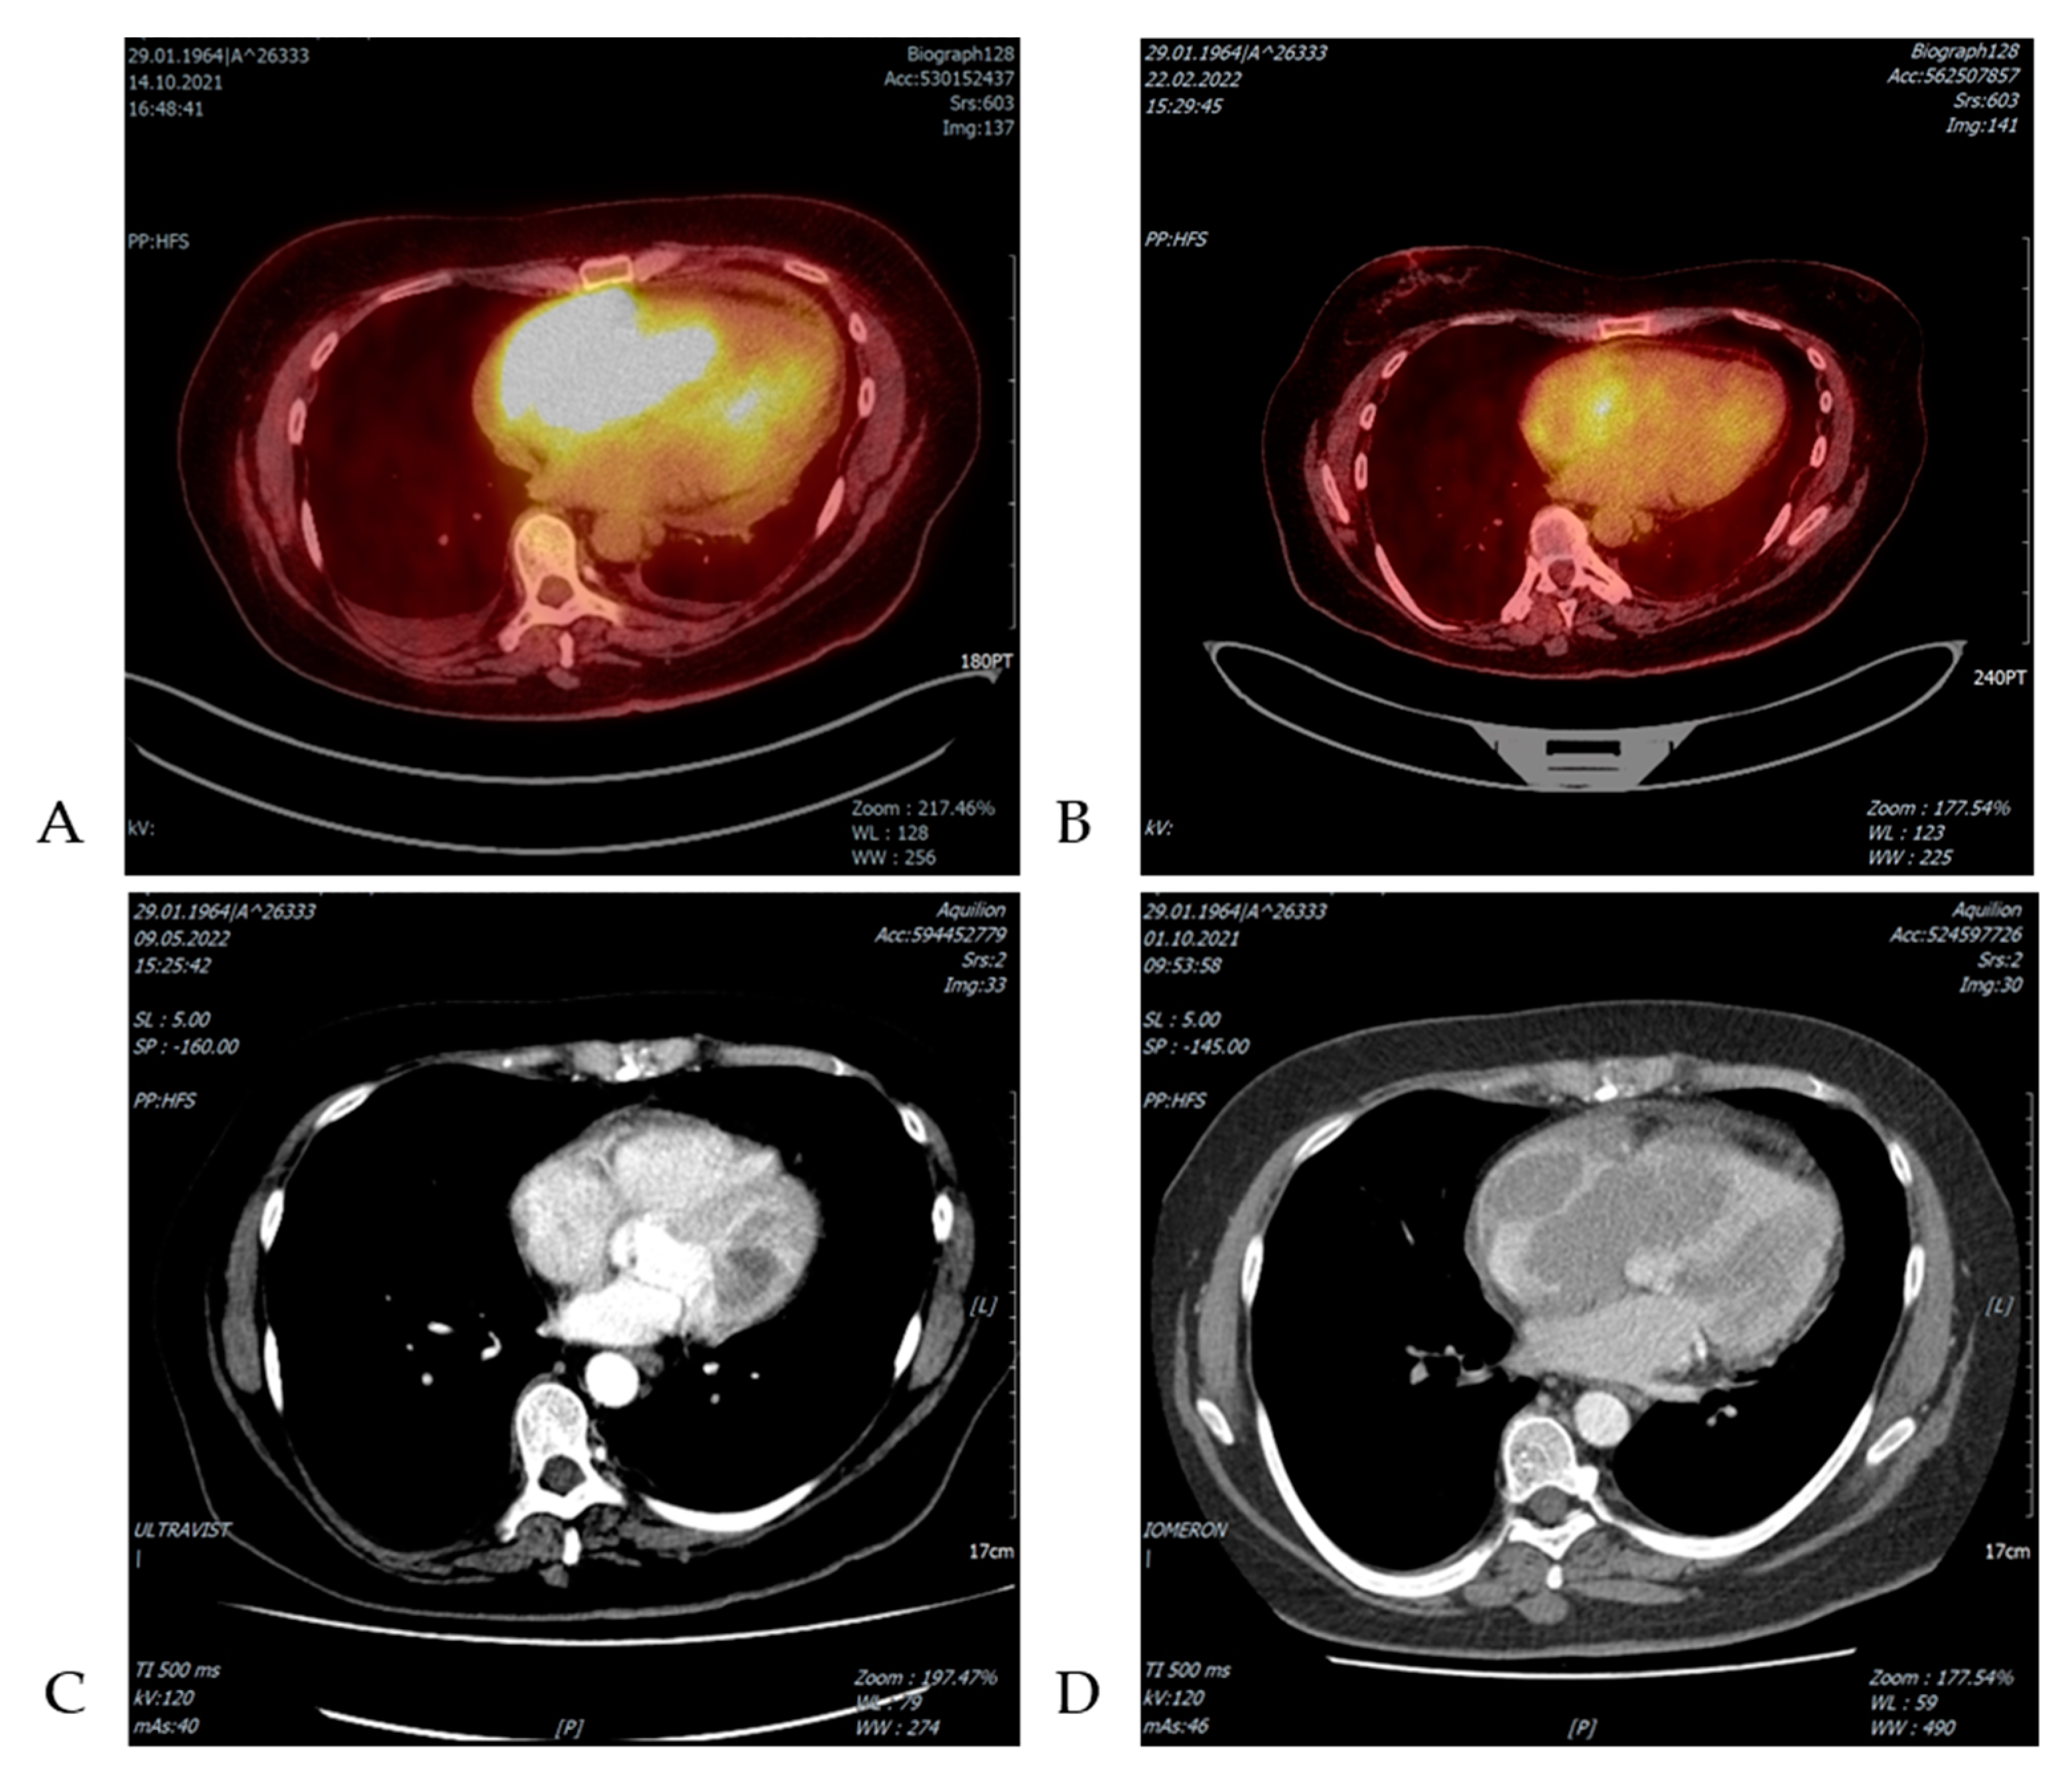

| Marra et al. 2021 [37] | 69/W | PB normal, SLL in BM biopsy | Rounded hypodense mass (41 × 58 mm) invaded the right atrium and the interatrial septum revealed by cardiac ultrasound and PET/CT scan | Right atriotomy with tumor mass resection + 6 R-CHOP | Alive and in complete remission at 42 months |

| Pudis et al. 2021 [38] | 75/M | CLL/SLL diagnosed before RT symptoms | Isolated cardiac involvement, PET/CT scan revealed a large cardiac mass in the right atria with high metabolic activity. Biopsy confirmed the diagnosis of DLBCL. | Not reported | Not reported |